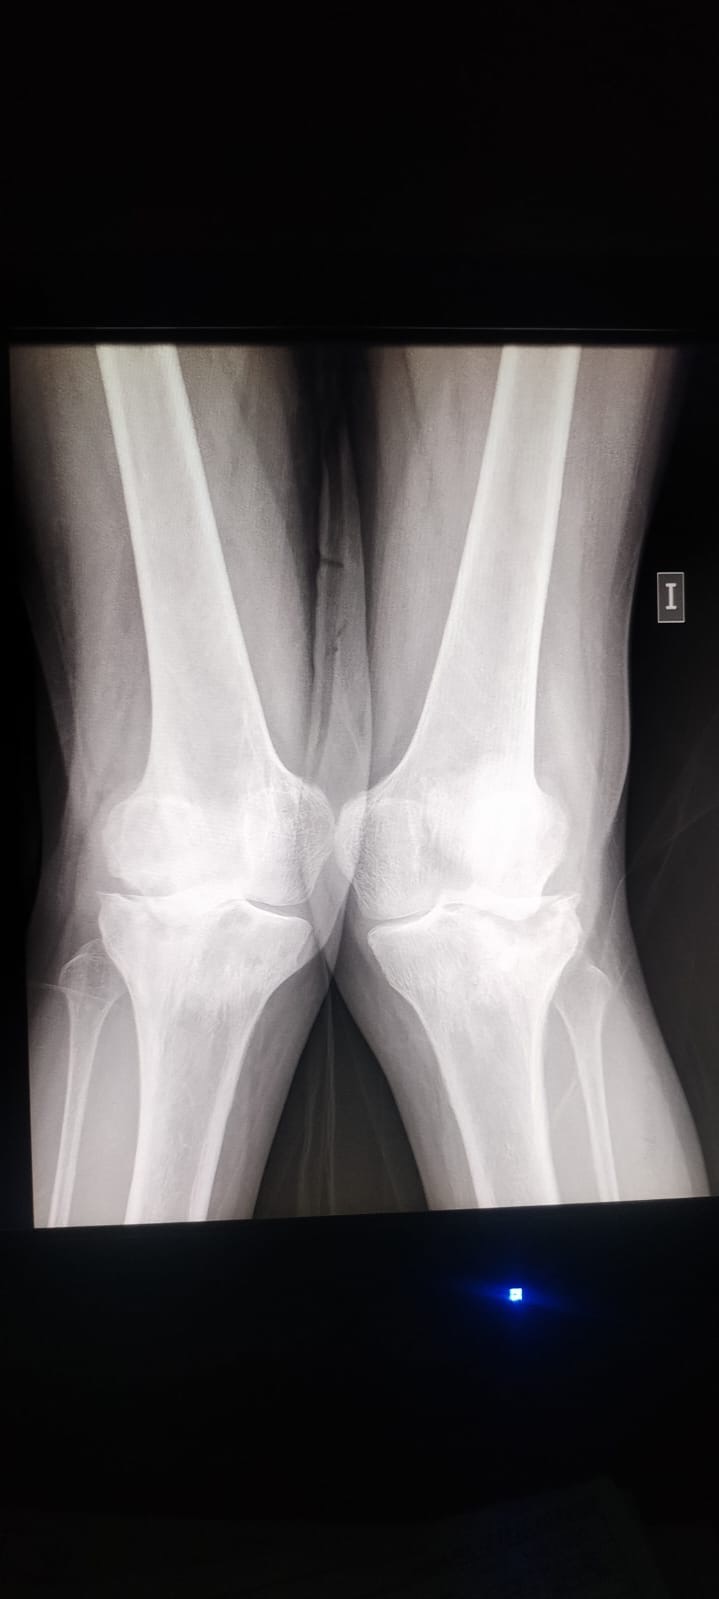

Debido a la forma en la que camino, el cartílago de ambas rodillas se ha desgastado por completo, y ahora los huesos chocan entre sí. Esto me genera un dolor constante e incapacitante que me impide moverme con libertad y trabajar como antes.

Necesito con urgencia prótesis en ambas rodillas para poder volver a caminar, trabajar y vivir sin dolor.